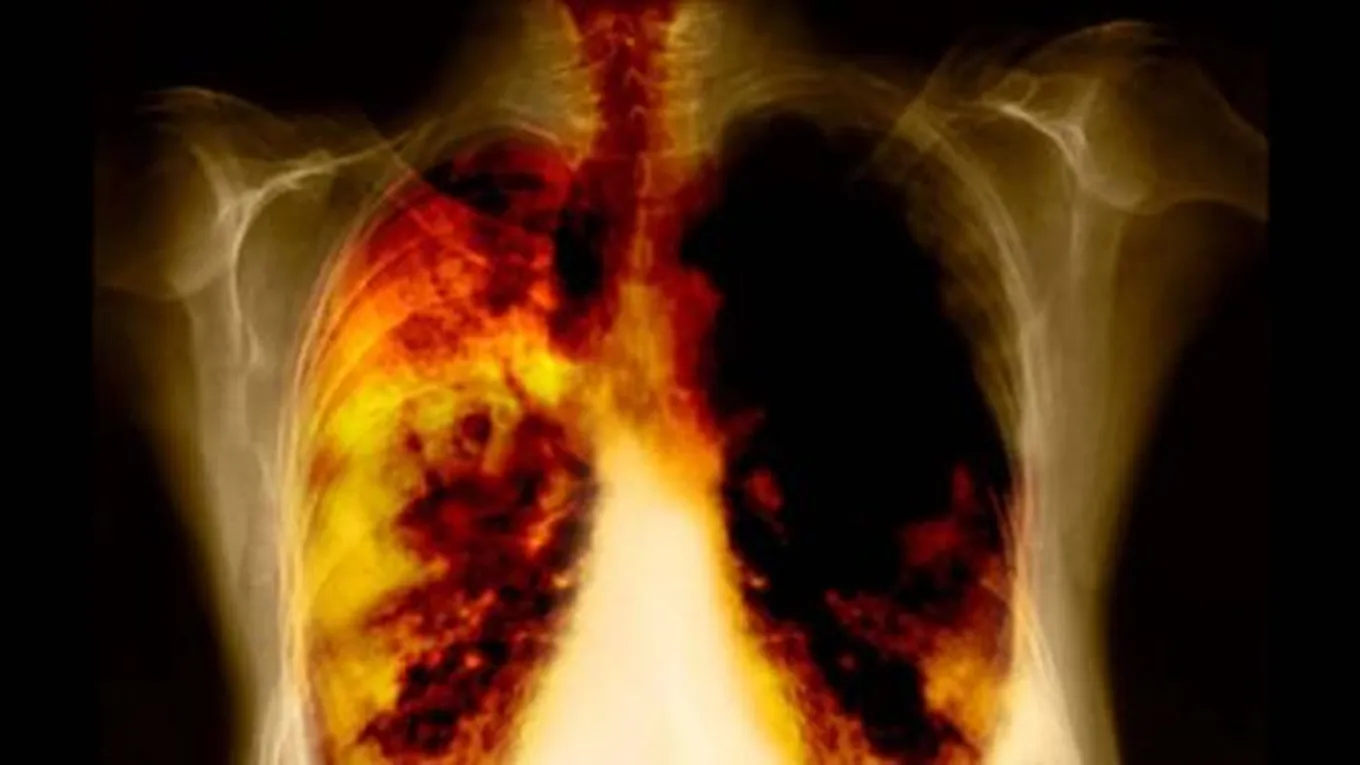

الأمراض الرئوية

يمكن للتدخين أن يؤدي إلى تعطيل وظائف الرئة بشكلٍ كبيرٍ، حيث يؤدي إلى إحداث تلفٍ في الشعب والجيوب الهوائية الصغيرة، والعديد من الأمراض الرئوية الأخرى التي قد تكون خطيرةً جداً، كسرطان الرئة على المدى الطويل نسبياً، وفي حال كان الشخص يعاني مسبقاً من الأمراض الرئوية والربو، فإنّ التدخين يؤدي إلى تفاقم تلك المشاكل بشكلٍ أسرع.[3]